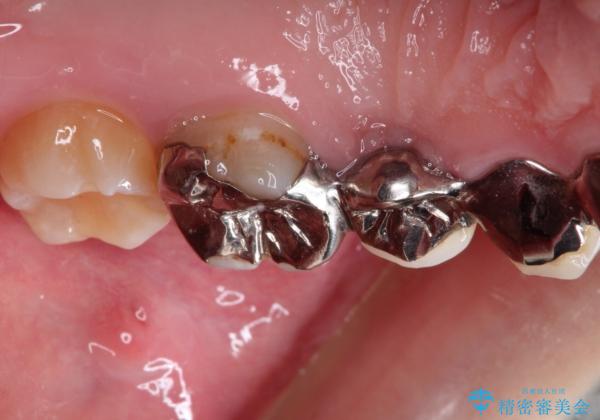

また奥歯にまたがるブリッジも金属のもので、適合もよくありませんでした。

オールセラミックによるやりかえを行いました。

色調もまわりの歯に合わせて、形態も患者様のご希望に沿うように製作させていただきました。